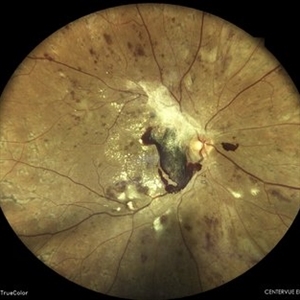

COATS' DISEASE

Mar 14 2022 by Akansha Sharma

MONTAGE OF A 11 YEAR OLD MALE WITH COATS' DISEASE

Photographer: Dr. Akansha Sharma-Retina Foundation, Ahmedabad

Condition/keywords: Coats' disease, exudates, telangiectatic vessels